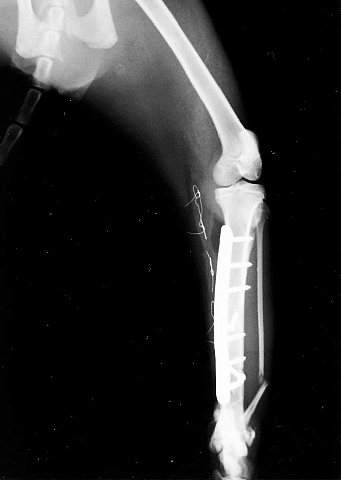

次も猫ですが、これは他院からさんざん脅かされて(?)転院してきた症例です。これはいわゆる「すね」のところが長い亀裂で折れていると同時に、実は小さい破片にもなってました。

すねの所は太い骨とそれを支える細い骨の2本で形成されています。写真を見ていただくと分かりますが細い方の骨は「あっち」に向いてますが、これは手術後に筋肉に引っ張られて自然に元の位置に戻ってくっついてきます。なので手術自体は本幹である太い方だけで大丈夫なんです。ただし大型犬の場合は細い方の骨にもプレートやピンで固定する必要があります。